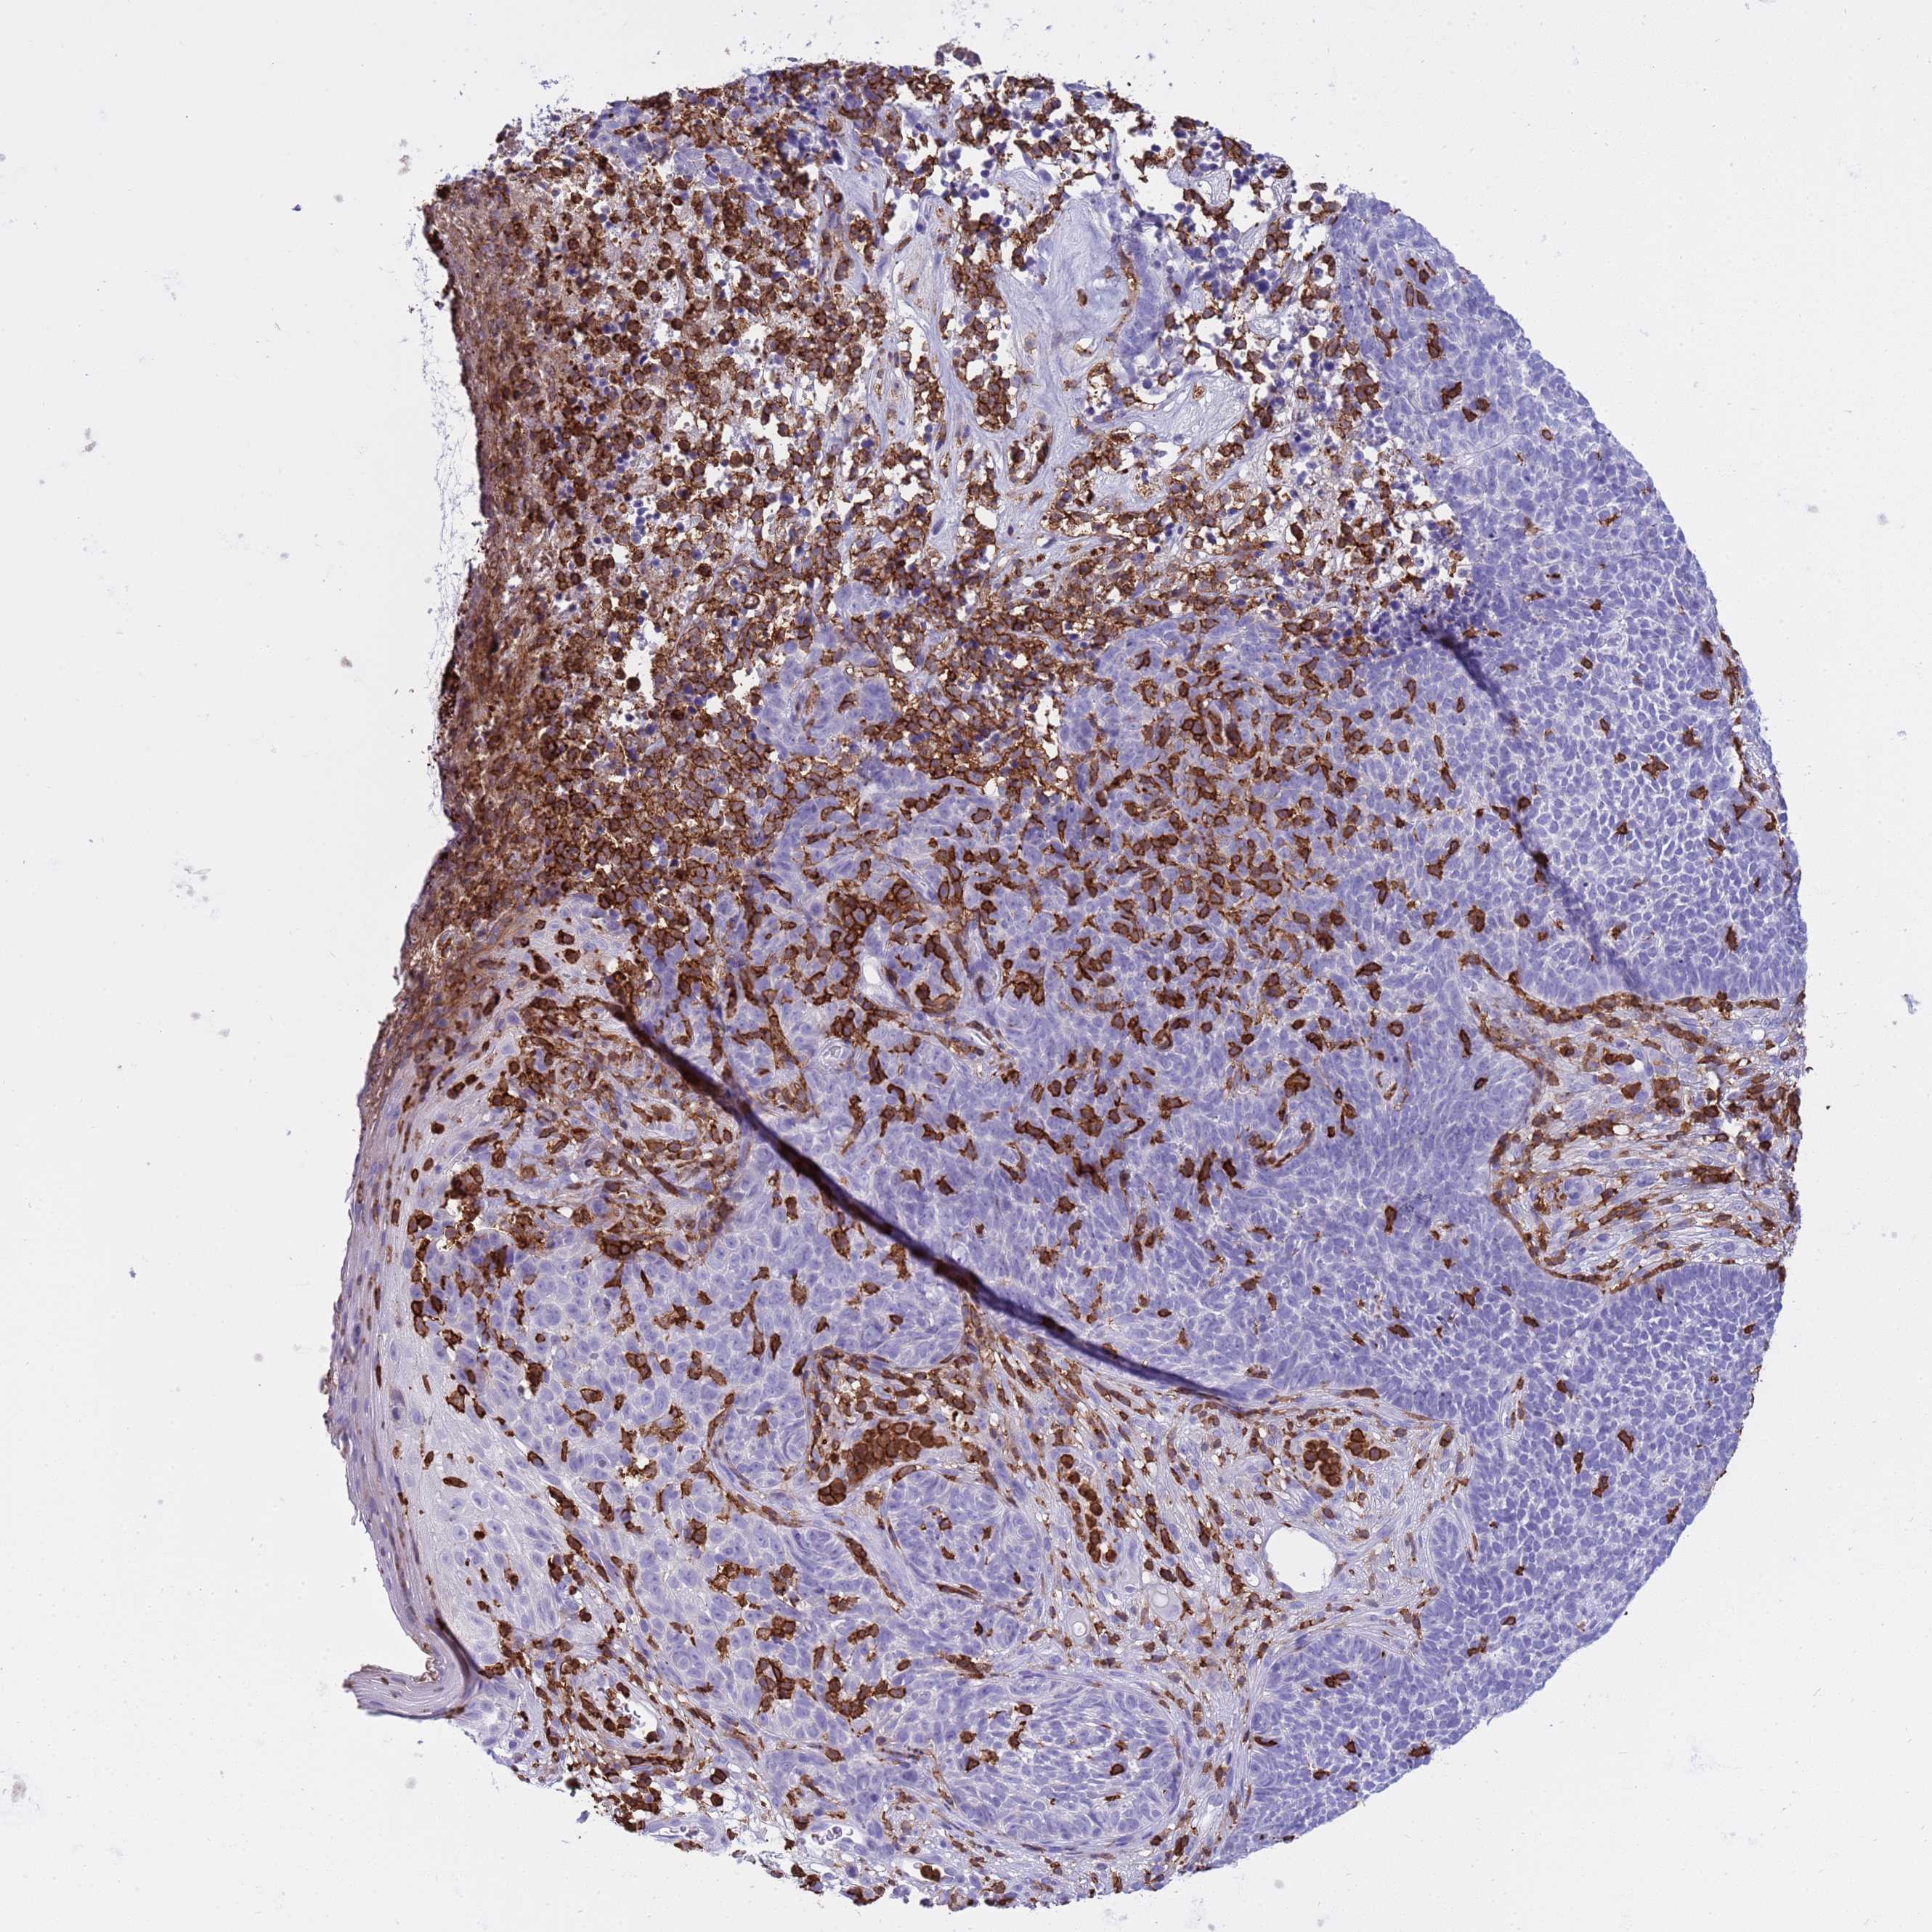

SKIN CANCER - Protein expressioni

A mouse-over function shows sample information and annotation data. Click on an image to view it in a full screen mode. Samples can be filtered based on level of antibody staining by selecting one or several of the following categories: high, medium, low and not detected. The assay and annotation is described here.

Antibody stainingi

Antibody staining in the annotated cell types in the current human tissue is reported as not detected, low, medium, or high, based on conventional immunohistochemistry profiling in selected tissues. This score is based on the combination of the staining intensity and fraction of stained cells.

Each image is clickable and will lead to virtual microscopy that enables deeper exploration of all samples and also displays staining intensity scores, fraction scores and subcellular localization as well as patient and tissue information for each sample.

Squamous cell carcinoma, NOS